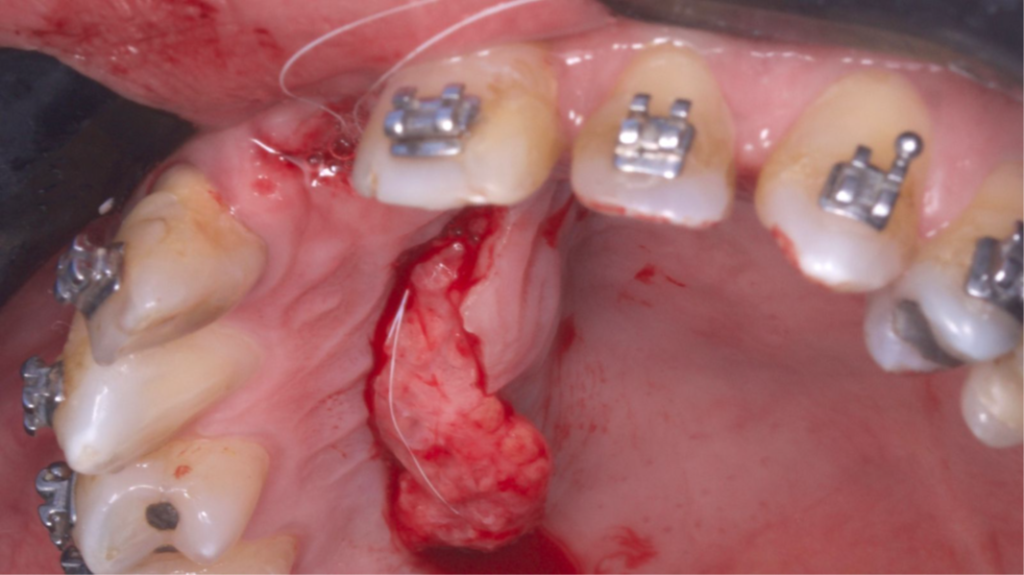

O retalho VIP–CT, inicialmente idealizado para a proteção de enxertos em área anterior de maxila, pode também ser usado para aumento de rebordo na região anterior, apresentando benefícios em comparação com outras técnicas de enxertos de tecidos conjuntivos por obter um enxerto próximo ao leito receptor e completamente viável (por se manter com pedículo), bem como pode evitar a exposição de uma regeneração óssea guiada (ROG) ou enxertos ósseos de grande morbidade, como com a técnica de Khoury ou enxertos onlay.

Paciente do sexo masculino encaminhado pela Ortodontia para a instalação de um implante ao nível do dente 1.1 (Figura 1), com diastemas mésio-distais de 2mm, para utilização do implante como ancoragem absoluta e melhor andamento da movimentação ortodôntica.